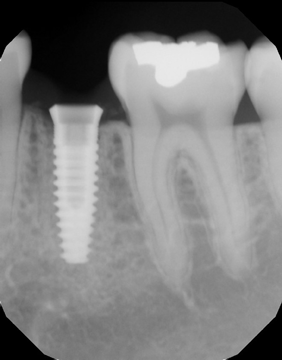

When the guide arrived, Yari was working in the office, so between her filing insurance claims for patients and checking in patients, she became my “next” appointment.During the implant placement, I captured several intraoral radiographs to verify the placement of the implant (Fig. 9). Using the guide offered precision placement. I placed the implant in 15 minutes, and she went back to work. To restore, I covered the screw hole with Grandio A2 (VOCO); a screw-retained crown (ProEsthetic Lab) was placed (Fig. 10).

Fig. 9 Fig. 10